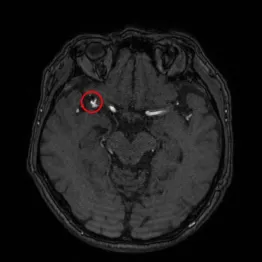

中でも最も多く使われているのが、19年10月に発売された「EIRL Brain Aneurysm(エイル・ブレイン・アニュリズム)」。脳MRI画像からくも膜下出血の原因となる「脳動脈瘤(りゅう)」の疑いのある部分を、AIが自動で検出する医用画像解析ソフトウエアだ。全国約120施設に導入されている。

国内の大規模調査では、3ミリ以上の未破裂の脳動脈瘤は破裂する可能性があるとされる。エイル・ブレイン・アニュリズムは、2ミリ以上の袋の形をした嚢状(のうじょう)動脈瘤に類似した候補部分を検出しマーク表示する。

通常、医師は脳MRI画像を目視で動脈瘤の疑いのある部分を探す(読影)が、その脳をスライスした画像は一患者当たり200枚前後に及ぶ。実際の最終的な診断結果は医師が決めるが、エイル・ブレイン・アニュリズムをサポートに使うことで読影の負担が減り、見逃しを防ぐことが見込めるわけだ。